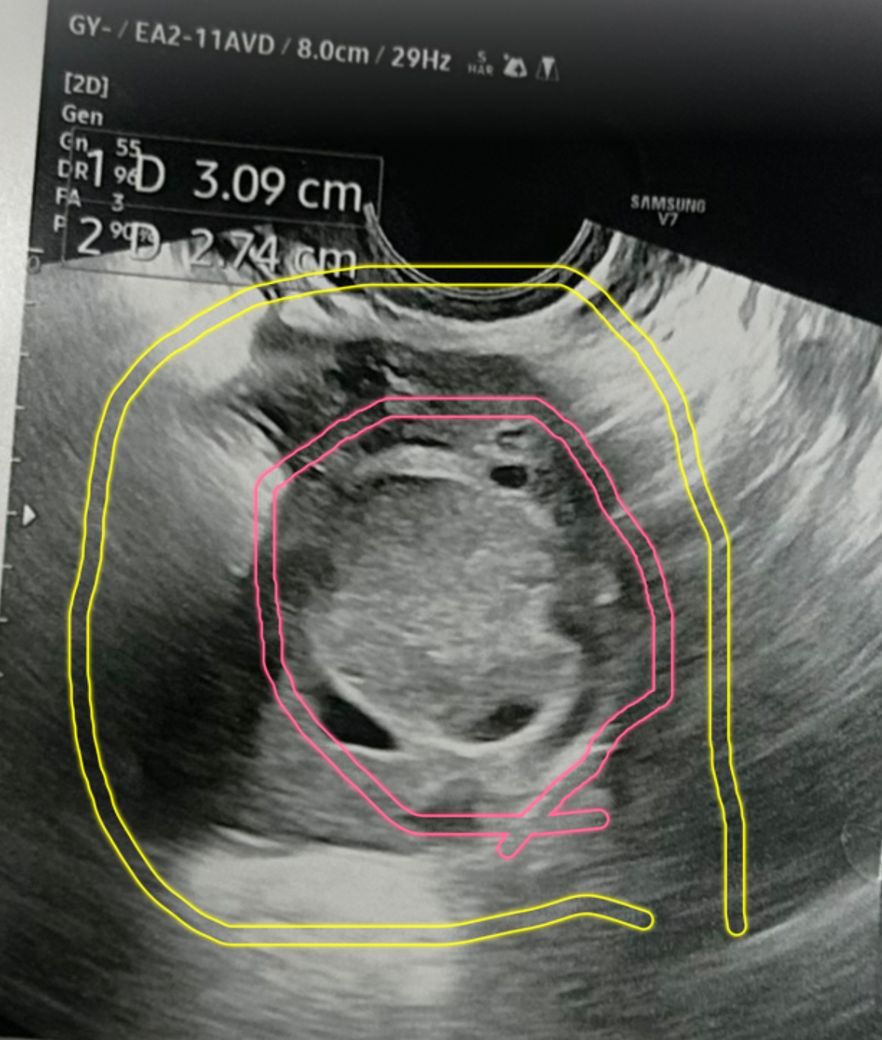

오른쪽 배가 너무 아파서 초음파를 했는데

단순 cyst 는 아니라하고 추적관찰하자고

하는데 뭘까요?

노란색원이 난소고 빨간색 원이 혹입니다.